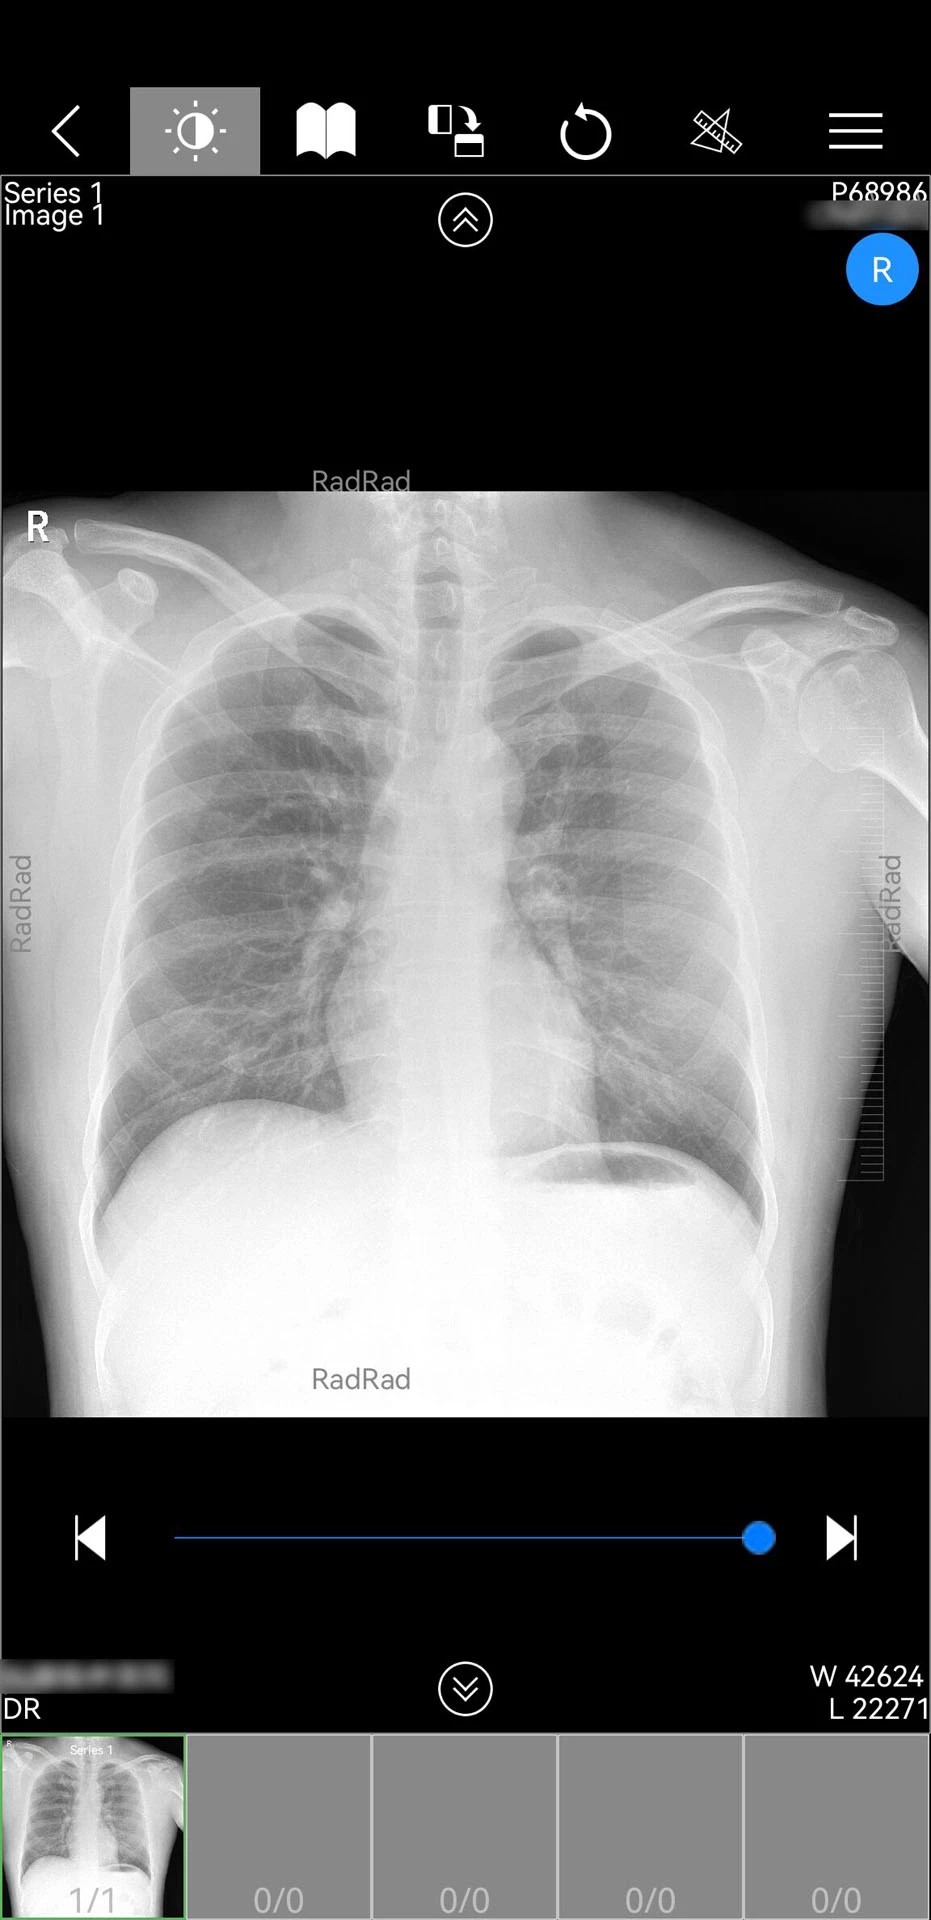

1. 多模态影像调阅:支持DICOM格式的CT、MRI、X光等医学影像的实时加载与多窗口对比,医生可缩放、旋转、测量病灶尺寸,并标注关键区域生成诊断报告。例如,2025年12月更新的v1.18.110版本新增CT三维处理服务,可自动生成肺部结节的3D模型,辅助医生评估肿瘤形态与周围组织关系。

2. 跨平台兼容性:支持Android 4.0及以上系统,适配主流手机与平板设备,界面采用全中文可视化设计,操作手势符合移动端习惯(如滑动切换影像序列、长按保存截图)。例如,医生在急诊场景下可快速调阅患者影像,无需依赖专用工作站。